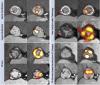

Objectives: The authors sought to assess whether 18F-fluoride positron emission tomography (PET)-computed tomography (CT) can detect bioprosthetic aortic valve degeneration and predict valve dysfunction.

Methods: Explanted degenerate bioprosthetic valves were examined ex vivo. Patients with bioprosthetic aortic valves were recruited into 2 cohorts with and without prosthetic valve dysfunction and underwent in vivo contrast-enhanced CT angiography, 18F-fluoride PET, and serial echocardiography during 2 years of follow-up.

Results: All ex vivo, degenerate bioprosthetic valves displayed 18F-fluoride PET uptake that colocalized with tissue degeneration on histology. In 71 patients without known bioprosthesis dysfunction, 14 had abnormal leaflet pathology on CT, and 24 demonstrated 18F-fluoride PET uptake (target-to-background ratio 1.55 [interquartile range (IQR): 1.44 to 1.88]). Patients with increased 18F-fluoride uptake exhibited more rapid deterioration in valve function compared with those without (annualized change in peak transvalvular velocity 0.30 [IQR: 0.13 to 0.61] vs. 0.01 [IQR: -0.05 to 0.16] ms-1/year; p < 0.001). Indeed 18F-fluoride uptake correlated with deterioration in all the conventional echocardiographic measures of valve function assessed (e.g., change in peak velocity, r = 0.72; p < 0.001). Each of the 10 patients who developed new overt bioprosthesis dysfunction during follow-up had evidence of 18F-fluoride uptake at baseline (target-to-background ratio 1.89 [IQR: 1.46 to 2.59]). On multivariable analysis, 18F-fluoride uptake was the only independent predictor of future bioprosthetic dysfunction.

Conclusions: 18F-fluoride PET-CT identifies subclinical bioprosthetic valve degeneration, providing powerful prediction of subsequent valvular dysfunction and highlighting patients at risk of valve failure. This technique holds major promise in the diagnosis of valvular degeneration and the surveillance of patients with bioprosthetic valves. (18F-Fluoride Assessment of Aortic Bioprosthesis Durability and Outcome [18F-FAABULOUS]; NCT02304276).